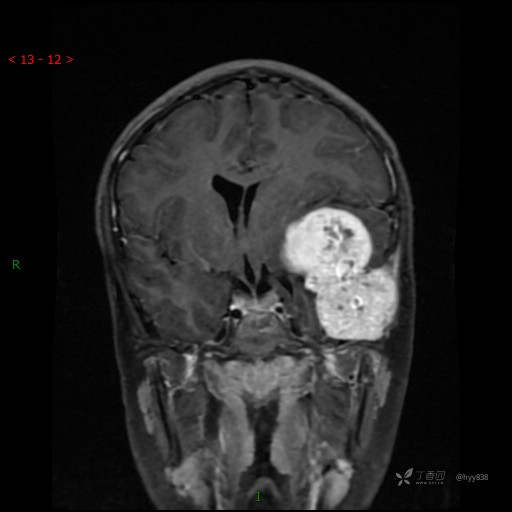

“典藏”病例分享。10岁儿童,头痛头晕一周余,CT、MRI 都有---结果公布~

患者年龄:10岁

主诉:头痛头晕一周余

简要病史:患者于一周前无明显诱因开始出现头痛头晕,无恶心呕吐,无肢体抽搐,无寒颤高热,无腹胀腹泻,无视力下降及视野缺损,上述症状休息后可稍缓解,未引起重视。 2天前患者头痛头晕不适加重,伴有恶心感,无呕吐,遂到当地人民医院行头颅CT检查示:左侧颞部占位性病变,今日家属为求进一步治疗,来我院门诊求治。门诊拟“左侧颞部占位性病变”收入我科。 患病以来,患者精神、饮食、睡眠尚欠佳,大小便如常,体力体重无明显变化。

临床诊断:左侧颞部占位

MRI增强